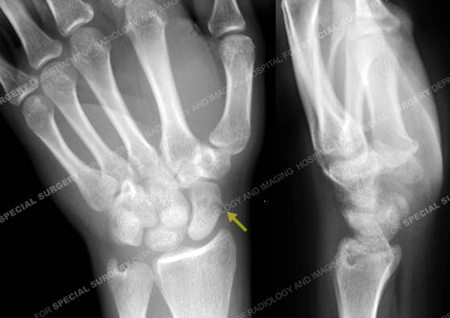

Anteroposterior radiograph revealing a scaphoid fracture (arrow).